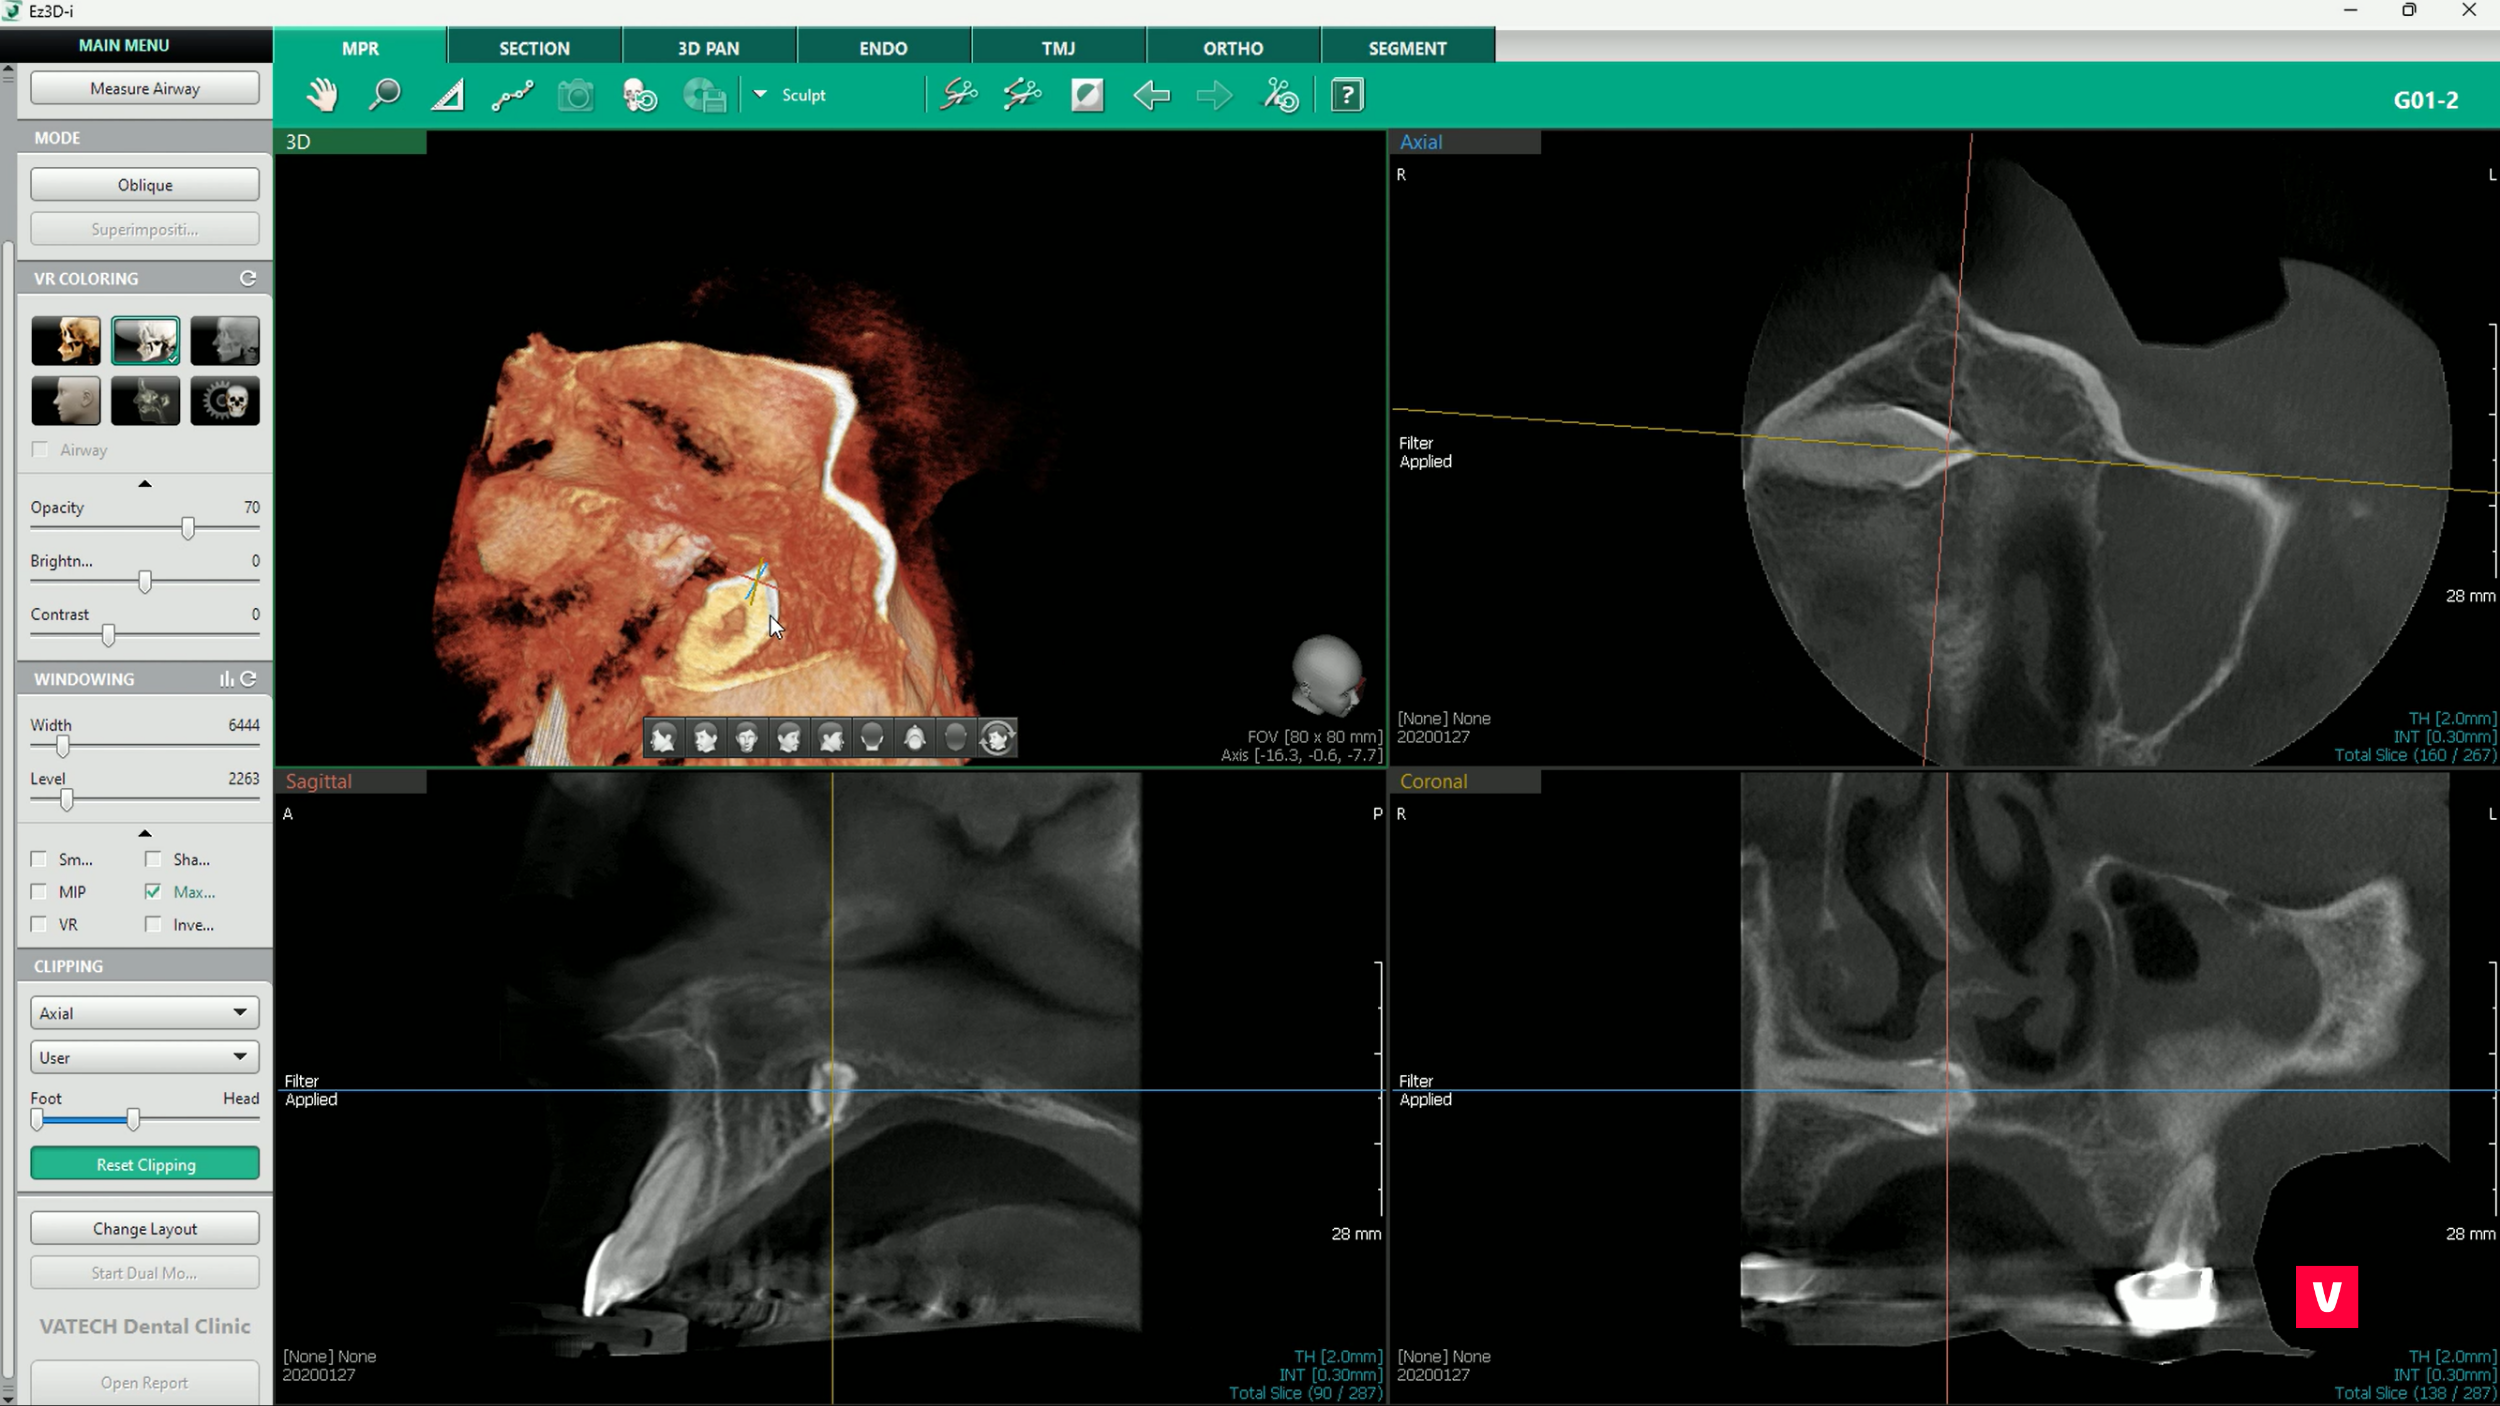

În studiul de caz pe care îl dezbatem în acest articol vom vedea cum depistarea unei astfel de complicații s-a putut observa doar în cazul unei examinări detaliate, ceea ce nu s-a putut observa după o scanare OPG (ortopantomografie), din cauza asimetriei din regiunea maxilarului. Doar cu ajutorul unei imagini CBCT 3D s-a văzut că pacientul are un dinte ascuns în regiunea maxilarului superior drept care ar fi putut provoca complicații grave dacă nu ar fi fost descoperit la timp.

Decuparea este o funcție excelentă pentru tăierea imaginii 3D și descoperirea structurilor anatomice ascunse. Aceasta poate ajuta la găsirea problemelor pe care imaginile OPG ar putea să nu le detecteze.

Există 3 planuri diferite de observare: axial, coronal și sagital. De asemenea, decuparea inteligentă este un instrument AI convenabil care ajustează automat planul vizualizat în imaginea 3D în funcție de unghiul de vizualizare.

În cazul de față, medicul a folosit tăierea pe un plan axial pentru a privi în os. Cu această funcție, este foarte ușor să descoperi orice structuri ascunse și să previi potențialele complicații.